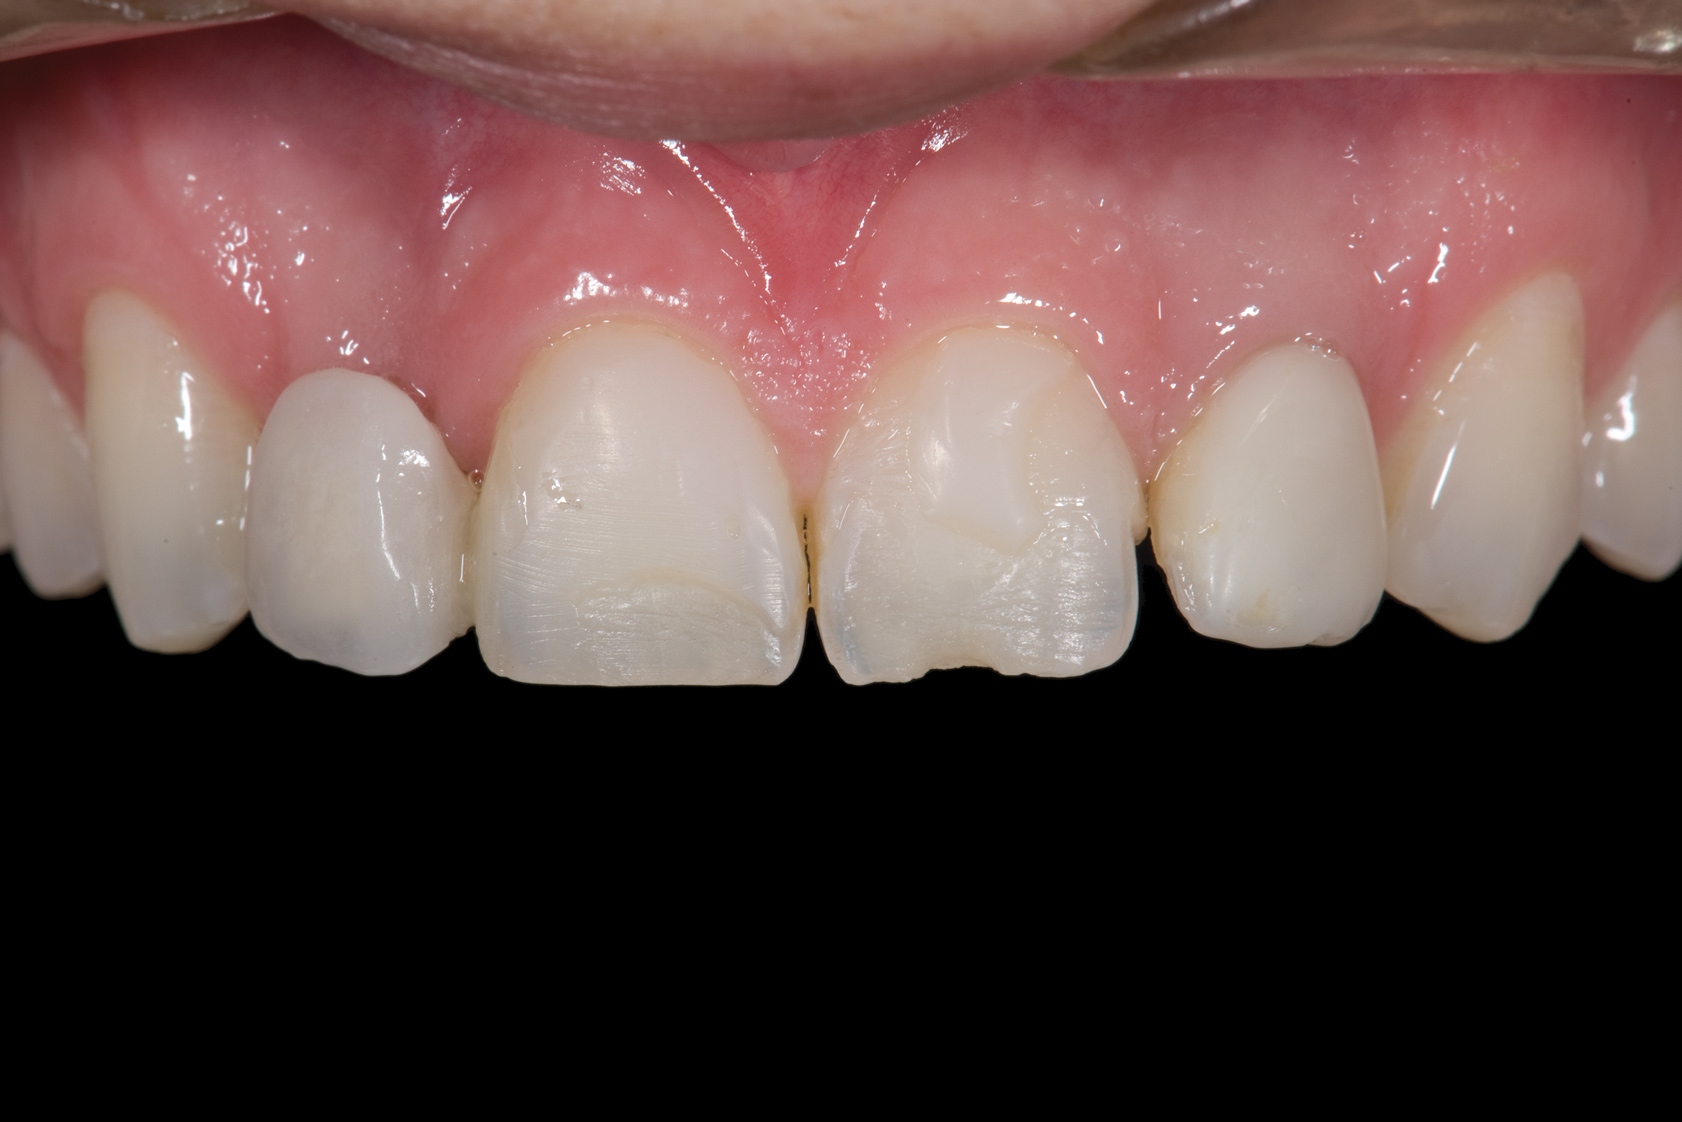

Fig 1. Initial presentation. Note midline shift to right, missing right lateral incisor, and diminutive left lateral incisor in crossbite.

Figure 1

A 14-year-old patient presented to the office with his mother (Figure 1). His chief complaint involved the large spaces between the teeth created by his missing right maxillary lateral incisor and his small left maxillary lateral incisor. He desired to replace the missing tooth with an implant and create a beautiful smile. Upon examination, he was found to have a Class I canine and molar relationship, but because he had a tooth size/arch size discrepancy and space distal to the right central incisor, the remaining incisors had drifted to the right. The left maxillary lateral incisor was peg-shaped and in a cross bite position. Studies have shown a clear association between congenitally missing teeth and reduced tooth size.59-62 Because he was only 14-years-old at the time and could not have implants placed until the cessation of growth (around 22 years old), he was sent to the orthodontist for alignment of the teeth.16,17